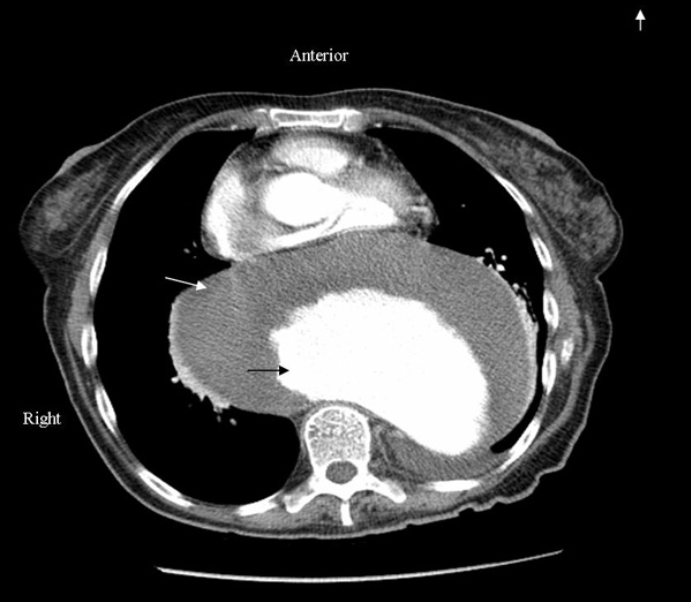

A 76-year-old female presented to primary care physician with a complaint of progressive dyspnea on exertion for three months. She denied chest pain, dizziness or back pain. She had been smoking two packs of cigarette per day for 50 years and had history of gastroesophageal reflux disease. Physical examination revealed decrease breath sounds in left lung field. Cardiac examination was unremarkable. Chest X-ray showed a large mass within the mediastinum and the left hemithorax (Figure 1). A contrast enhanced chest computed tomography scan demonstrated a large thoracoabdominal aortic aneurysm (TAA) measuring 11 cm at its greatest diameter in thorax compressing the left atrium (Figure 2). Circumferential thrombus was surrounding the true lumen but no contrast extravasation or leak was noticed. She was transferred urgently to our facility for further management. After complete preoperative work up repair of the thoracoabdominal aneurysm was planned.

Figure 2: Contrast enhanced CT scan demonstrating a large thoracoabdominal aortic aneurysm (black arrow) compressing the left atrium. Circumferential thrombus (white arrow) was surrounding the true lumen.